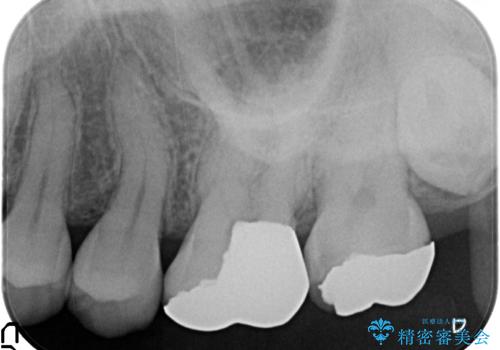

- 笑った時に目立つ銀歯を改善したいとのことで来院されました。

保険適応の銀歯を除去し虫歯を取ったのち、ジルコニアクラウンで置き換えていきます。

- 55万円(仮歯・ジルコニアクラウン×5)費用は治療当時の料金となります